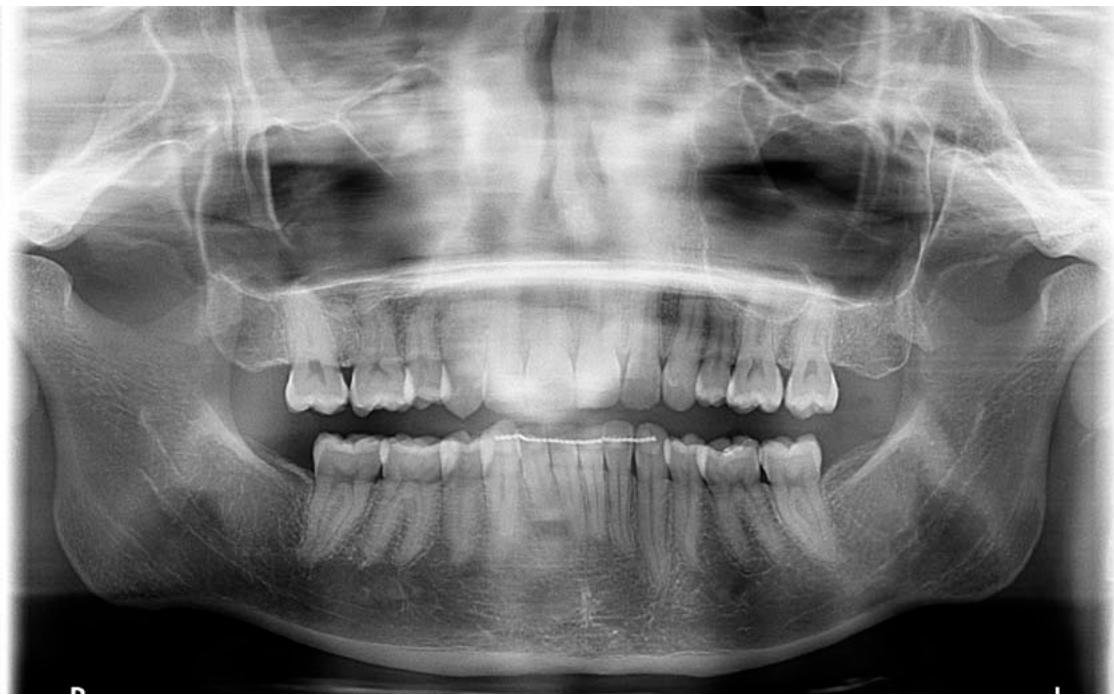

A l'examen radiographique, on observe que les dents de sagesse ont ete enlevees.

Orthopantomographie de début de traitement.